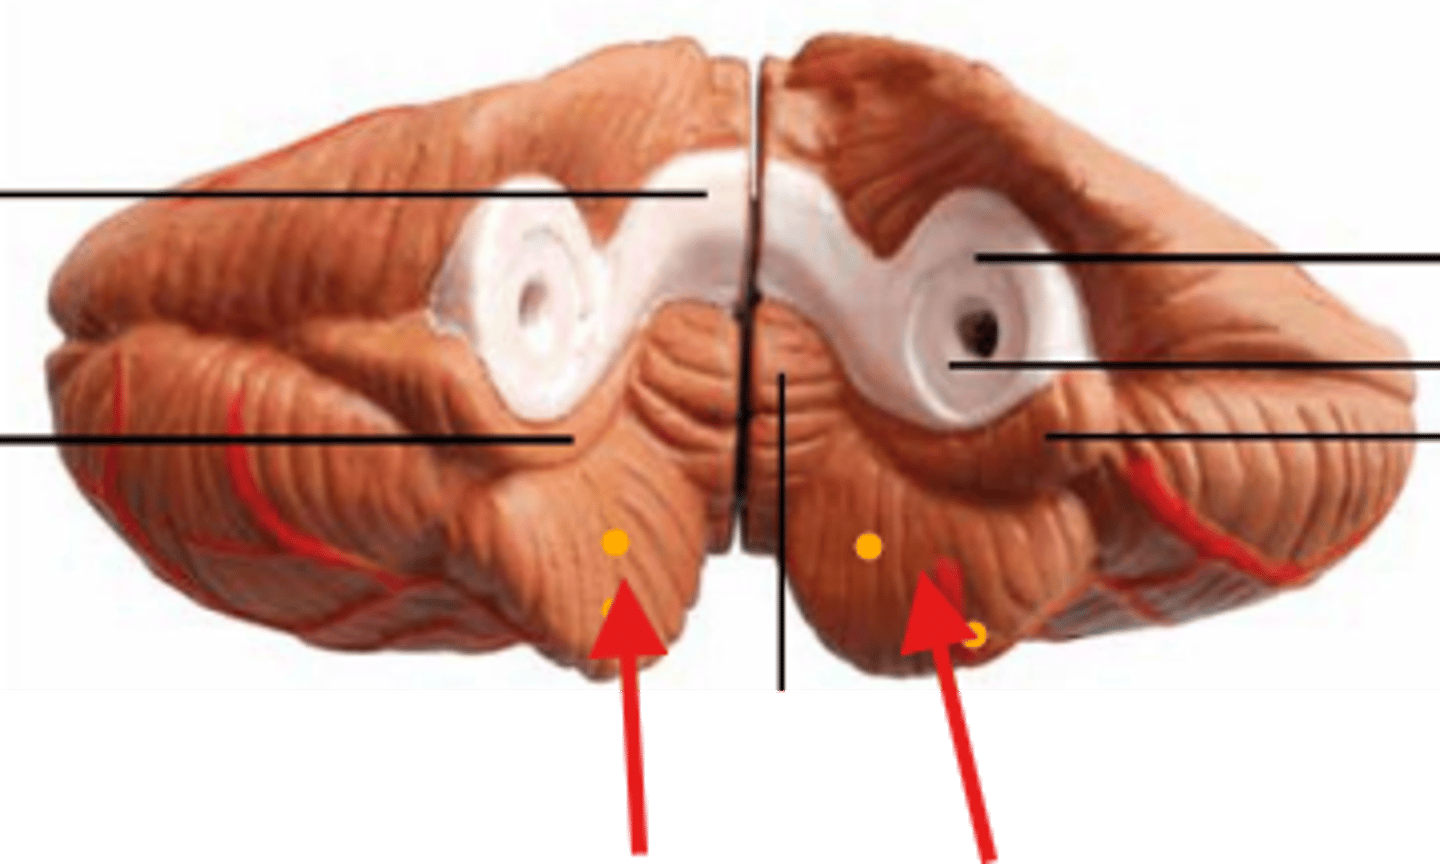

What is the red arrow pointing at?

what structure is the red arrow pointing at?

Red arrow is pointing at what?

Name the structure the yellow dot is on.